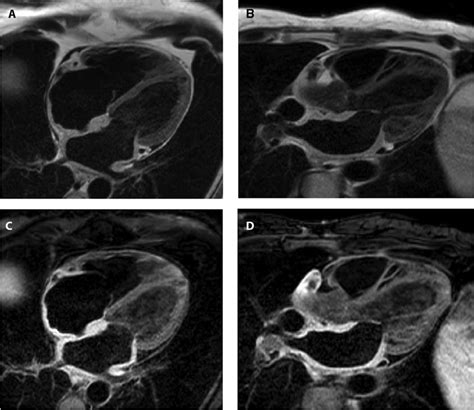

Cardiac MRI Identifies patterns of myocardial scarring and inflammation.